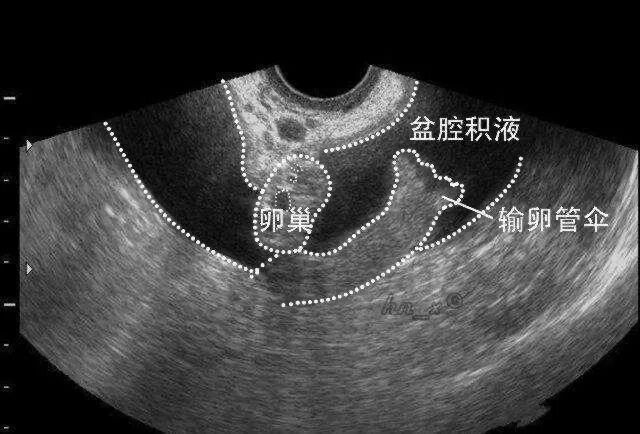

通常情况下,盆腔积液是看不到摸不着的,只有通过B超检查才能发现。平时我们检查看到的B超报告提示盆腔积液10——30毫米,大多数是没有问题的。盆腔积液只是一种表现,而不是一种疾病。

临床上,盆腔积液分为生理性和病理性。

▪生理性盆腔积液主要是由腹膜分泌、卵泡破裂后卵泡液的积储或者是月经血倒流引起。

▪病理性盆腔积液主要是由滤泡或者黄体破裂、盆腔炎性疾病、卵巢肿瘤、卵巢过度刺激综合征、输卵管异位妊娠破裂等因素引起。